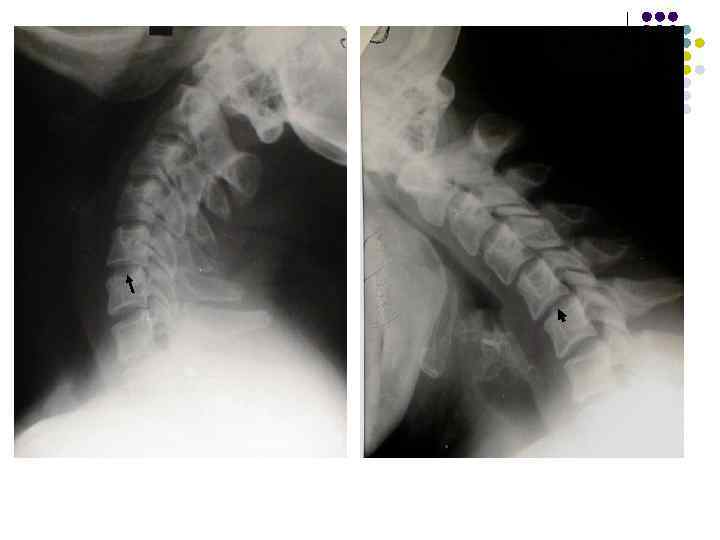

Обызвествления межпозвоночного диска • Чаще локальное обызвествление желатинозного ядра или отдельных участков фиброзного кольца • Редко обызвествляется весь диск • Часто сочетается с умеренным остеохондрозом передних участков диска • Как правило, не вызывает никаких субъективных и объективных симптомов, являясь случайной находкой

Обызвествление дисков

Обызвествление межпозвоночного диска